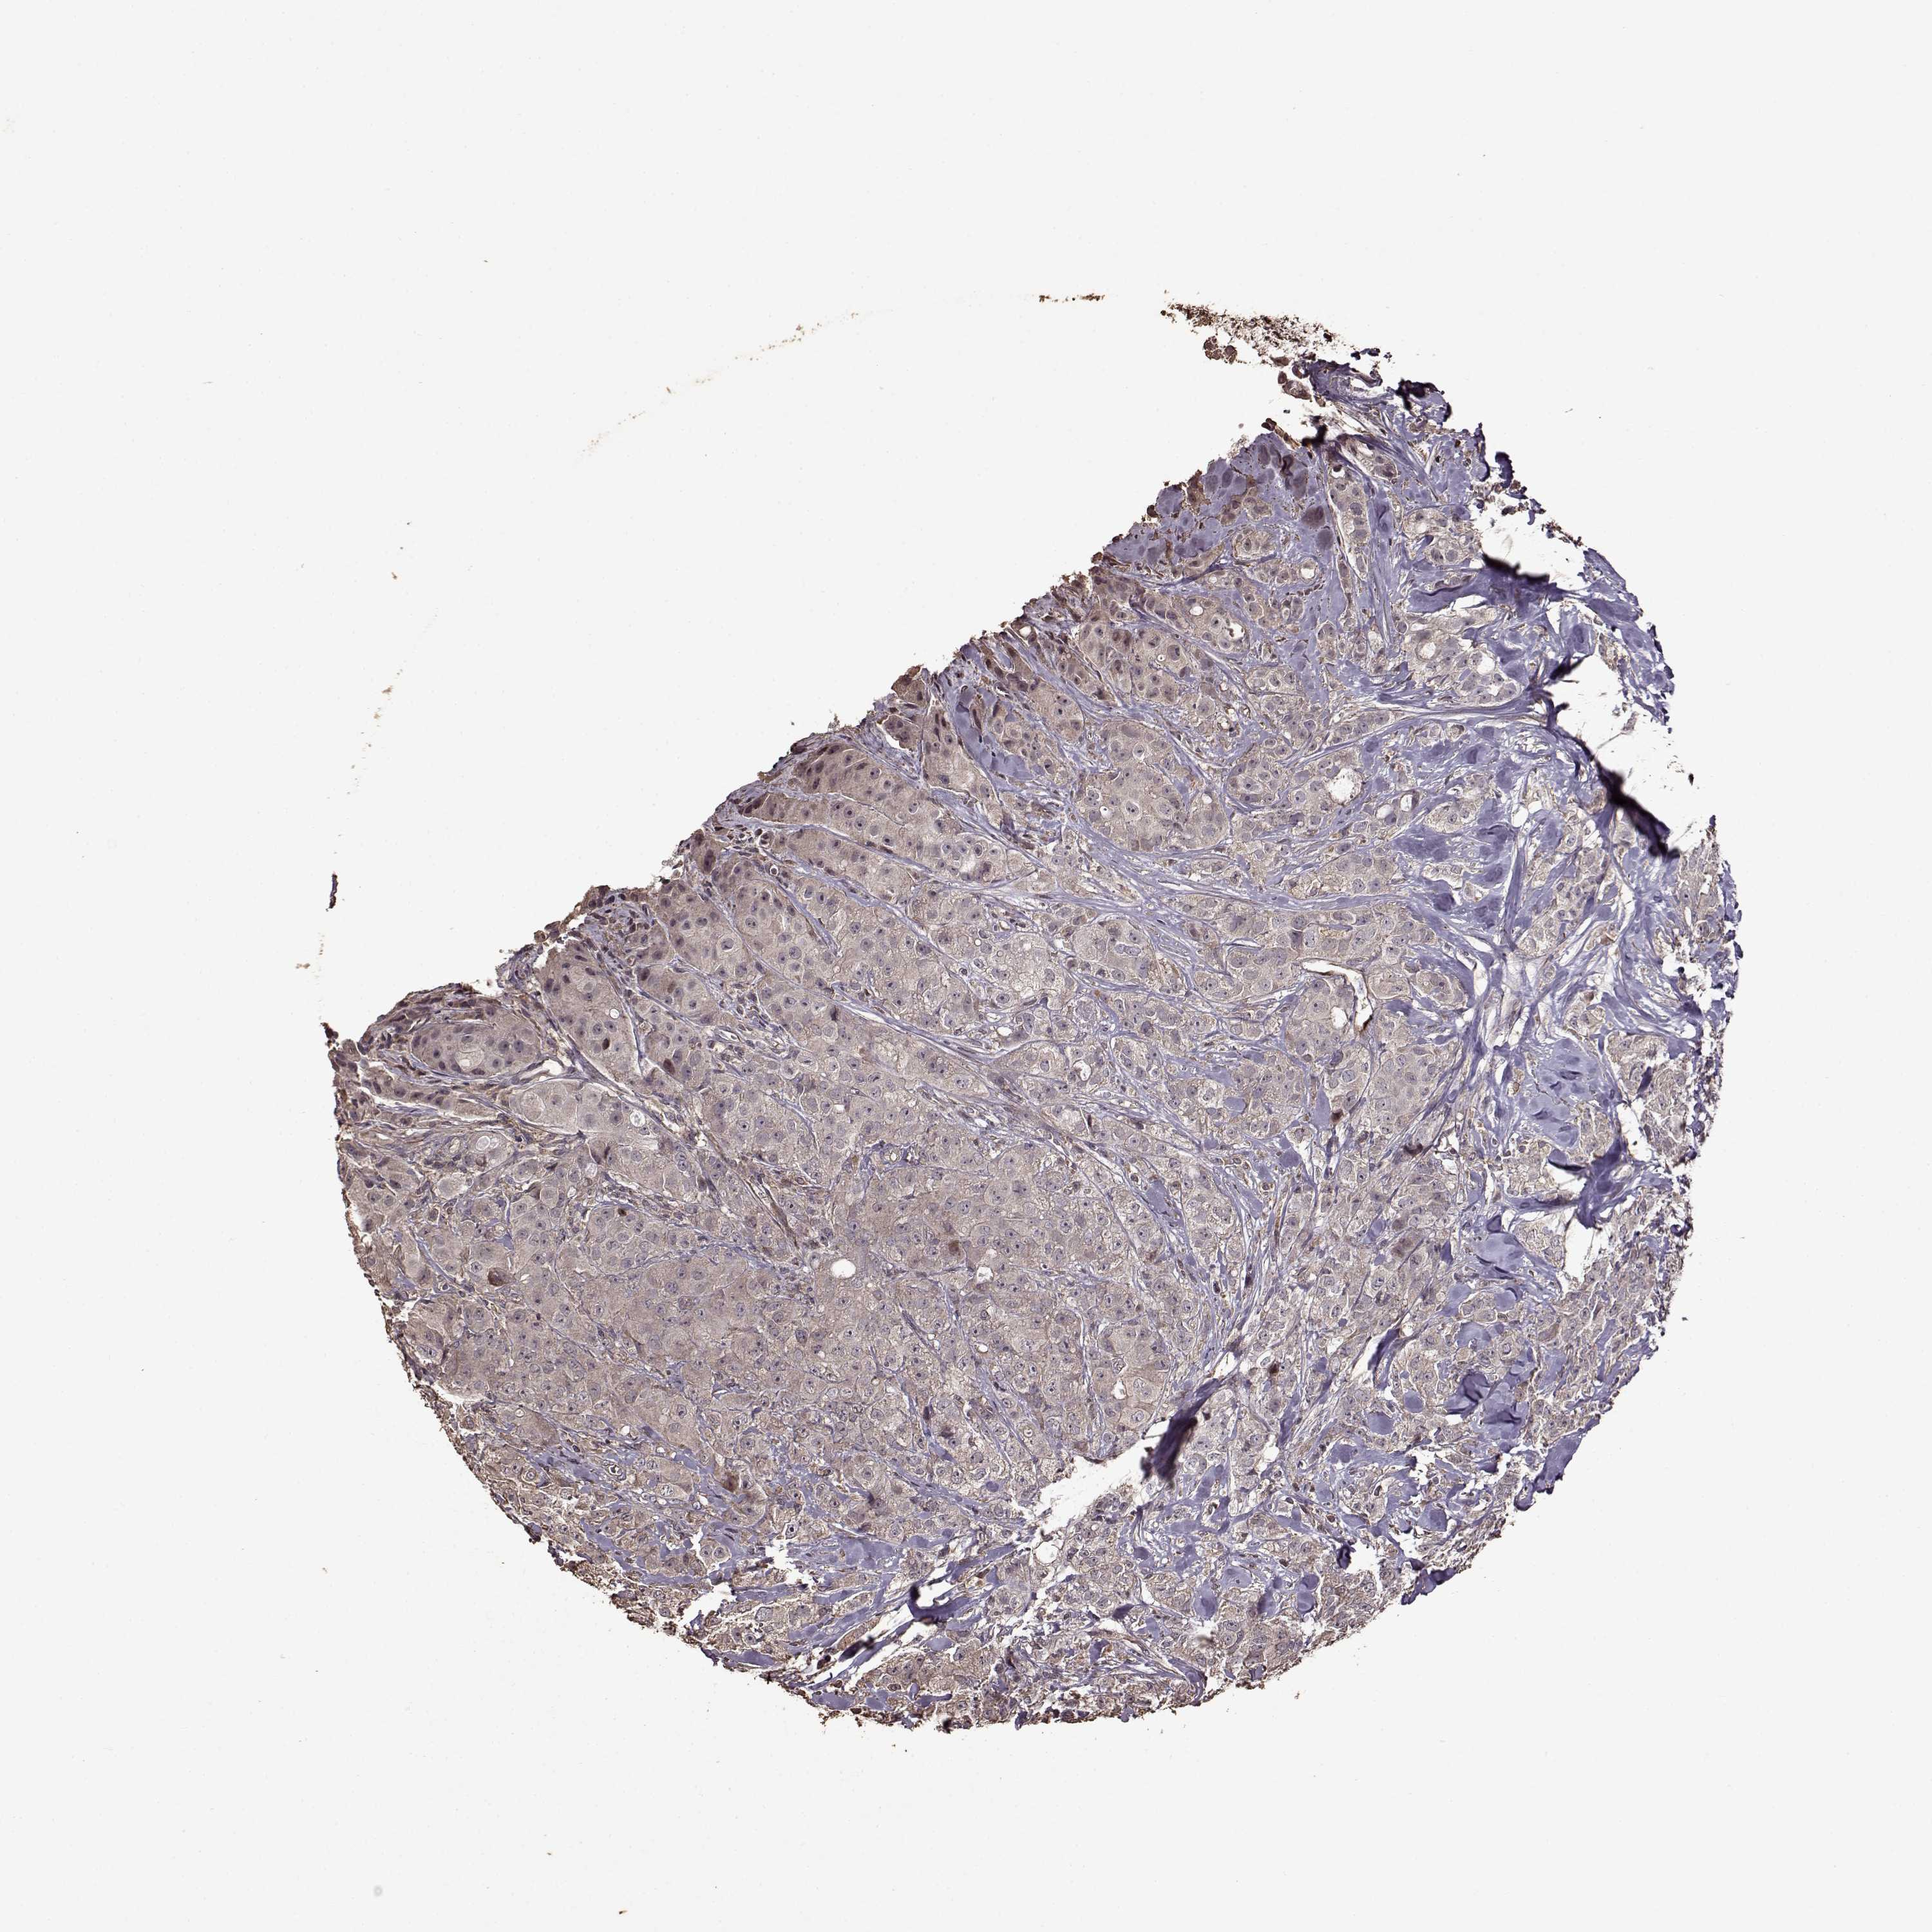

CANCER BREAST CANCER Show tissue menu

BRCA TCGA BRCA VALIDATION PROTEIN EXPRESSION